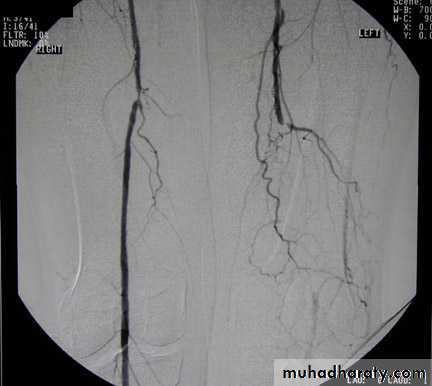

Angiography of iliac vessels